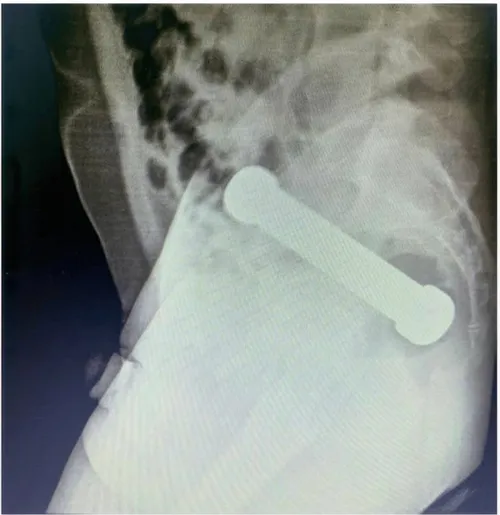

picture_vk_dumbell_brasil_02

Röntgenfoto van het bekken (zijaanzicht) waarop een vreemd voorwerp (halter/dumbbell) te zien is. (Foto: International Journal of Surgery Case Reports)